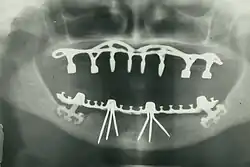

The modern movement of evidence-based dentistry calls for the use of high-quality scientific research and evidence to guide decision-making such as in manual tooth conservation, use of fluoride water treatment and fluoride toothpaste, dealing with oral diseases such as tooth decay and periodontitis, as well as systematic diseases such as osteoporosis, diabetes, celiac disease, cancer, autoimmune diseases, and HIV/AIDS which could also affect the oral cavity. Other practices relevant to evidence-based dentistry include radiology of the mouth to inspect teeth deformity or oral malaises, haematology (study of blood) to avoid bleeding complications during dental surgery, cardiology (due to various severe complications arising from dental surgery with patients with heart disease), etc.

By nature of their general training, dentists, without specialization, can carry out the majority of dental treatments such as restorative (fillings, crowns, bridges), prosthetic (dentures), endodontic (root canal) therapy, periodontal (gum) therapy, and extraction of teeth, as well as performing examinations, radiographs (x-rays), and diagnosis. Dentists can also prescribe medications used in the field such as antibiotics, sedatives, and any other drugs used in patient management. Depending on their licensing boards, general dentists may be required to complete additional training to perform sedation, dental implants, etc.

- Oral and maxillofacial radiology – the study and radiologic interpretation of oral and maxillofacial diseases.